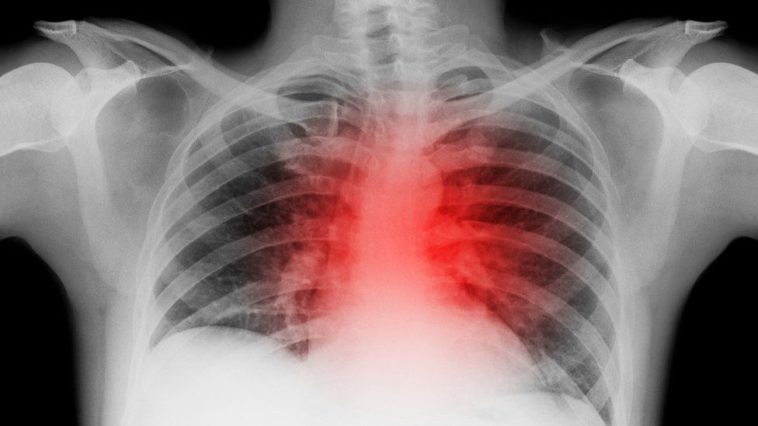

Covid: ‘Sharp drop’ in heart-attack hospital admissions

There has been a sharp drop in the number of patients admitted to hospitals in England with heart attacks or heart failure in recent months, research reveals.